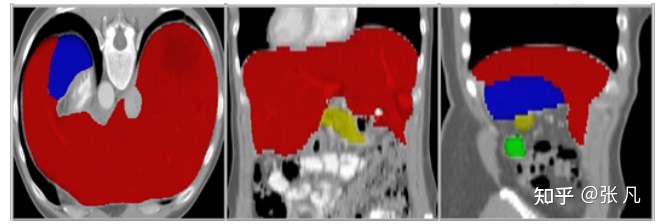

badcase主要包括器官病变和器官缺失,尤其是肾脏、肝脏病变case较多。

肝脏病变:

器官缺失: